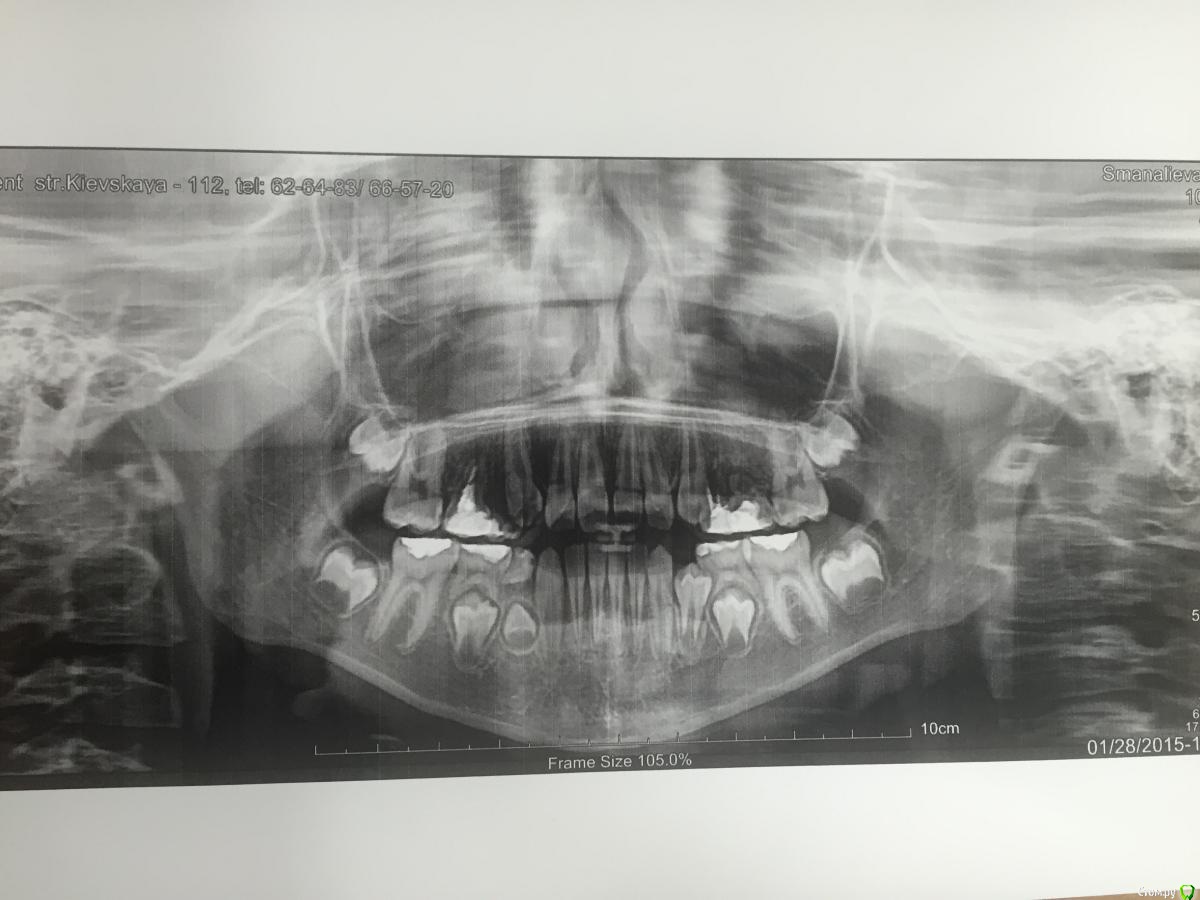

Дорогие коллеги, пожалуйста помогите определится с планом лечения. Пациенту 10 лет, отсутствуют зачатки 15 14 24 25 зубов.

По одной ОПТГ сложно определиться с планом лечения, еще есть диагностическая информация? На первый взгляд могу только предложить сделать прицельные 5.5  , 6.5, 6.4 зубов, кажется , что 5.5 можно полечить и оставить , еще в 2.6 и 1.6 кариозные полости на контактах.

Если лечить бессмысленно временные моляры, то их удаление и аппарат с искусственными зубами , который будет устранять и проблемы прикуса по сагиттали .Вообще вариантов лечения может быть много , чтобы не гадать , сделайте фото зубных рядов и трг еще , тогда обсуждение активнее пойдет.